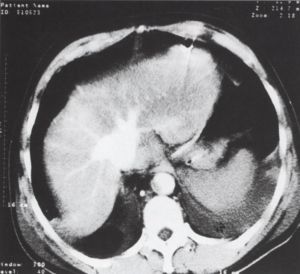

4. ábra.

A nagyított felvételen az aorta kifejezetten meszes intimájű, levált, ventral és jobb oldal felé nyomott. A valódi lumen erősen beszűkült.

5. ábra.

Dissectio mind az aorta ascendensben, mind az aorta thoracalisban, A dissectio a mellkasi aortában jól látható, mindkét lumenben kontrasztanyagot halmozó vér van. A kisebb, összenyomott lumen a valódi lumen (a nyíl a levált intimára mutat).